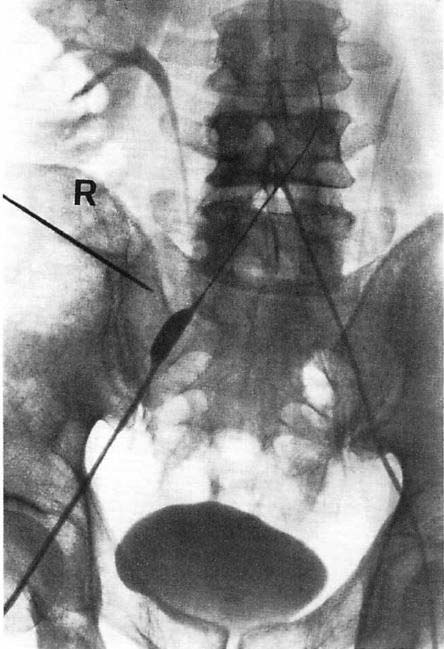

図3.膝窩動脈の完全閉塞.A.術前.B.カテーテル治療後.三分岐以下の動脈の再疎通が得られている.

【要旨・解説】下肢動脈の動脈硬化性狭窄,閉塞のカテーテルによる拡張術の報告で,その後Interventional Radiologyと呼ばれるようになる一連の手技の初報である.具体的には,鼠径部の大腿動脈を経皮的に順行性に穿刺し,ここからガイドワイヤを挿入してアテローマによる狭窄部を越えて遠位まで送る.これに外径0.1インチのカテーテルを被せてアテローマを通過させながら拡張する.可能であれば,これに外径0.2インチのカテーテルをさらに被せる.

当時,下肢動脈の閉塞性動脈硬化症の治療法としては,内膜剥離術,静脈グラフトなどがあったが,その適応がない場合は専ら下肢切断術が行なわれていた.ここでは下肢切断術が予定されていた9例11肢についてカテーテルによる血管拡張術を行ない,8肢で切断術を回避できた(図3).